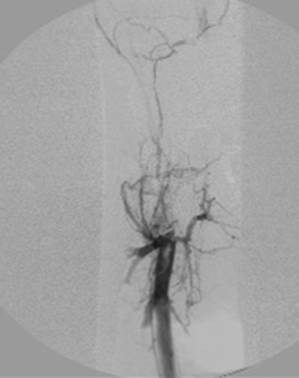

Eliminación razonable del trombo en las venas ilíacas tras una sola pasada del catéter DVX de AngioJet (25 mg de tPA en 250 cc de solución salina normal).

Venograma final tras la aspiración con catéter grande y tratamiento de la estenosis subyacente (debido a la compresión extrínseca del tumor) con un stent de 16 mm con el balón inflado a 12 mm.

Tiempo total: <90 minutos. Flujo interno perfecto de la parte posterior de la rodilla a la vena cava inferior (VCI).

Tras cuatro meses y medio; capacidad para caminar normal, sin hinchazón.